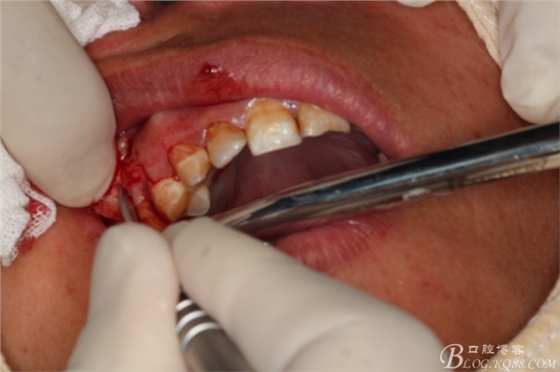

圖7.做角形切口

圖8.翻瓣